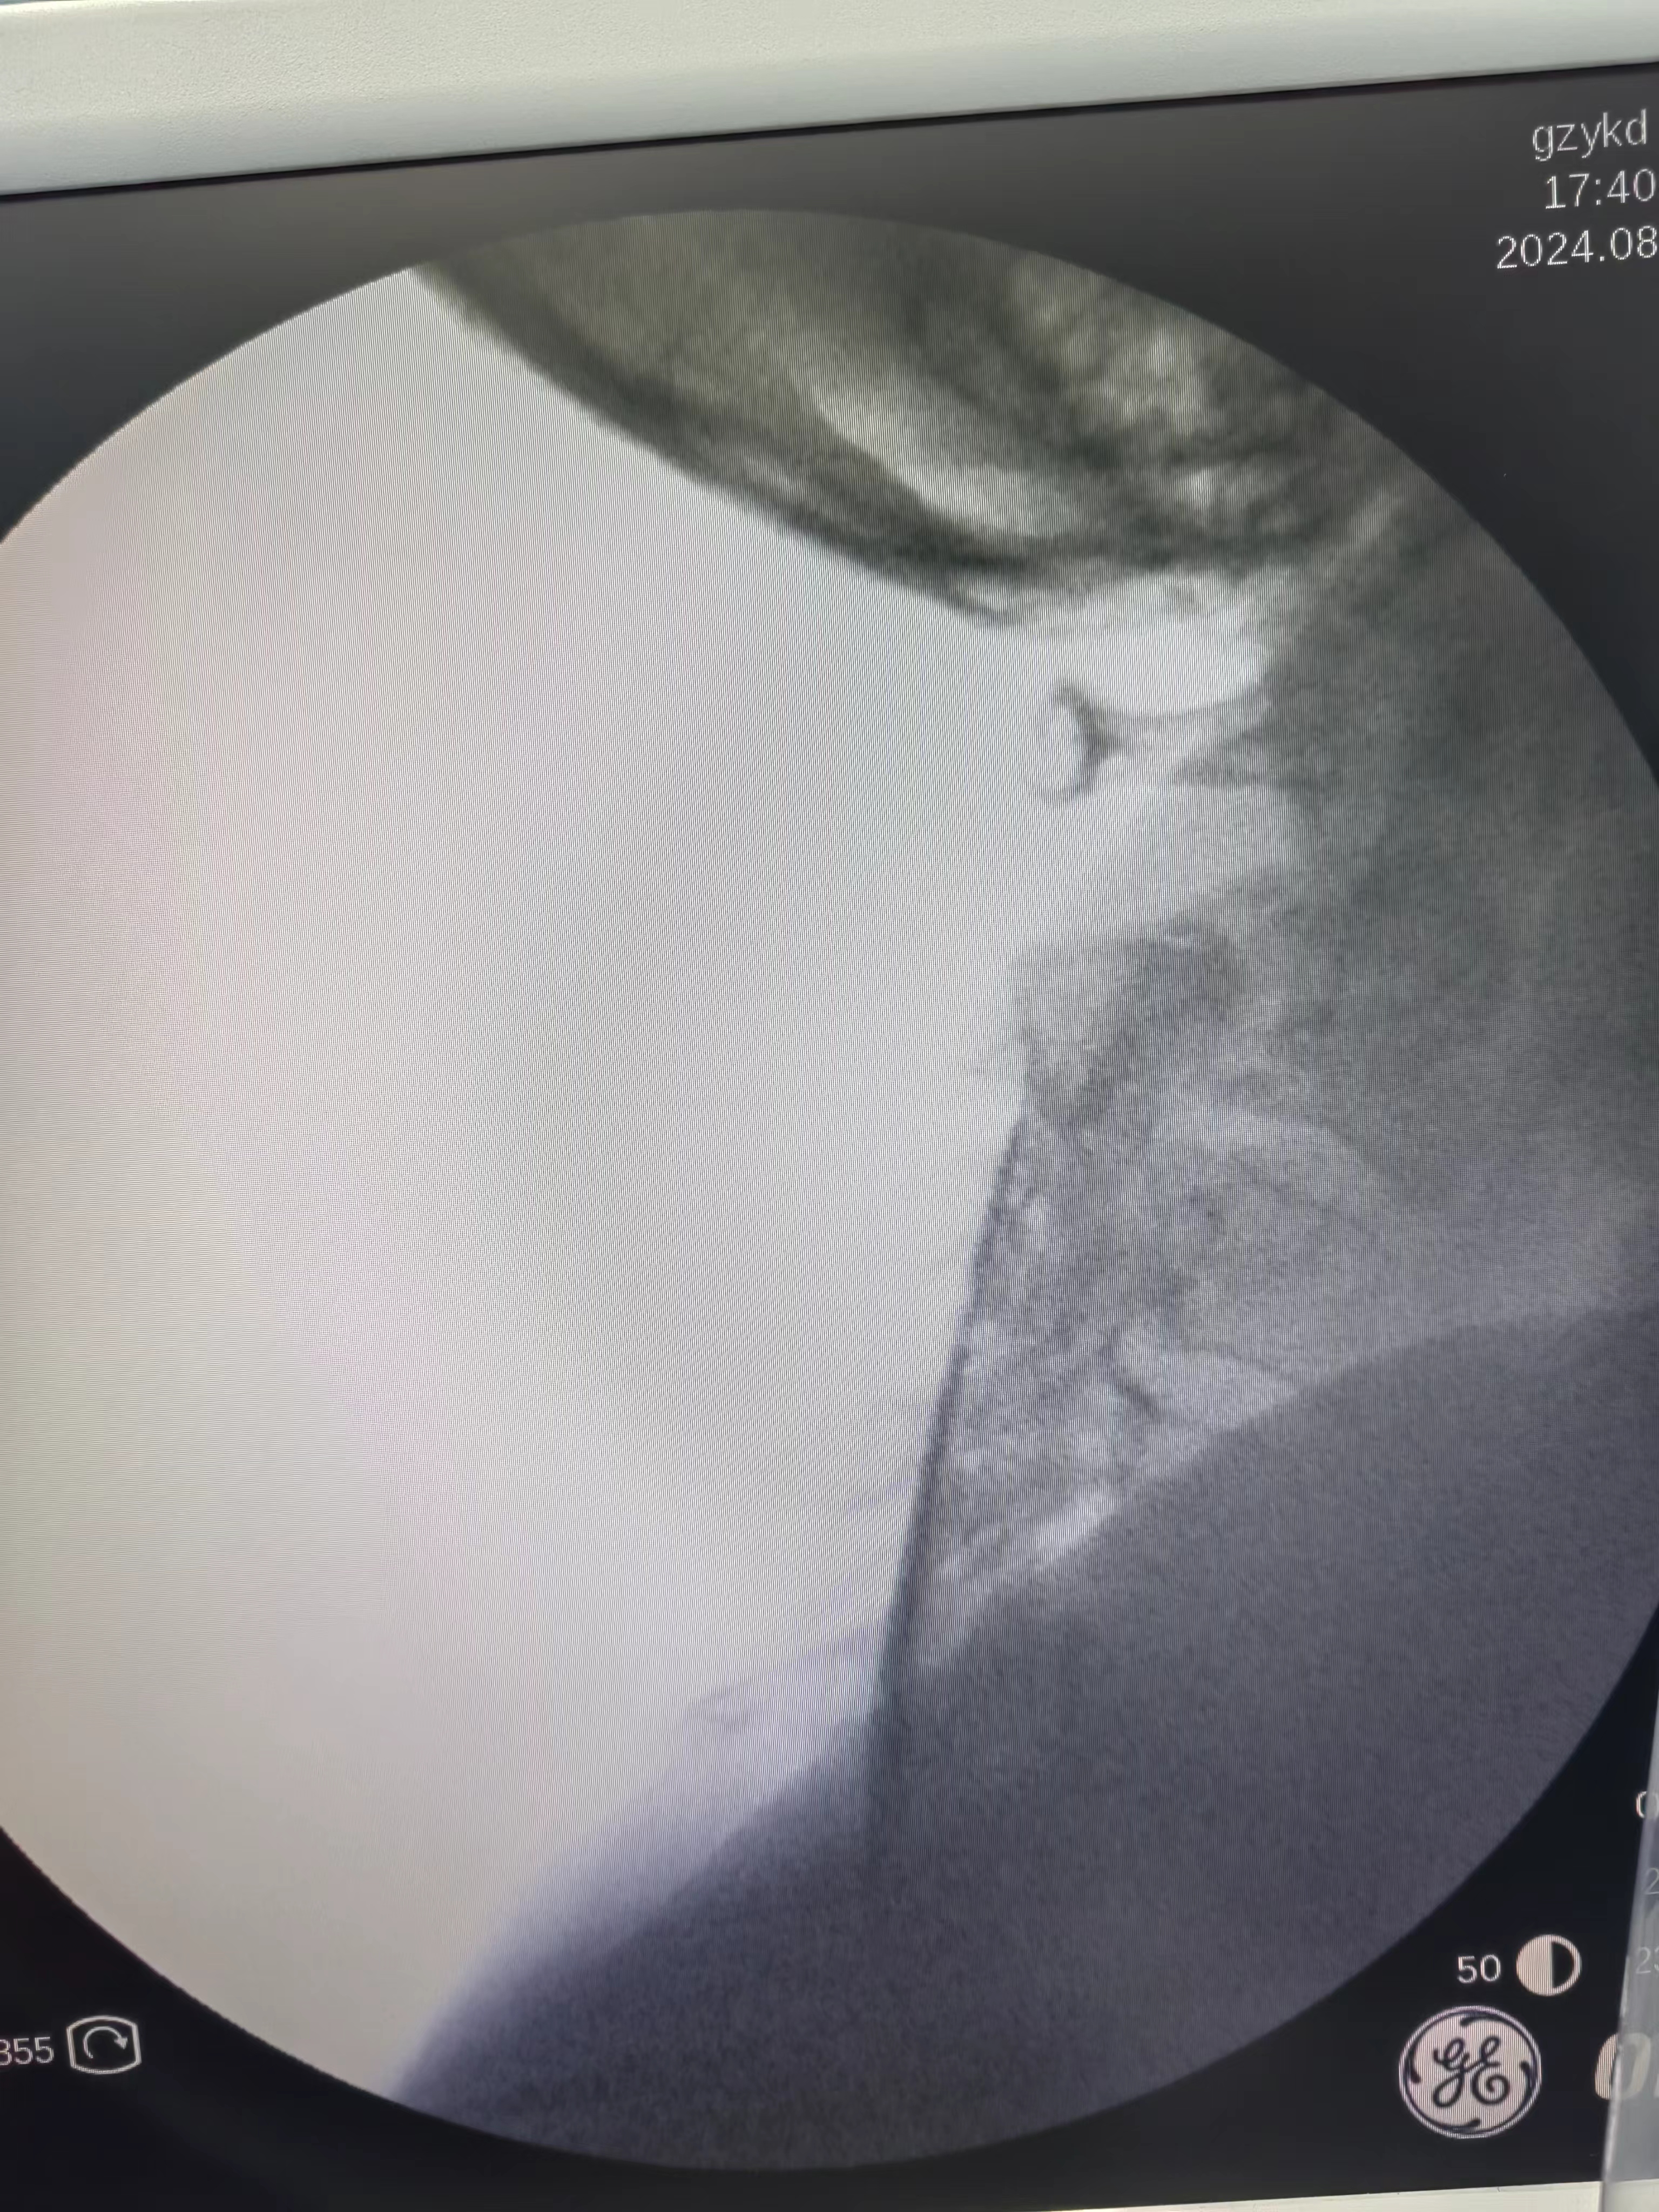

颈椎C臂透视下